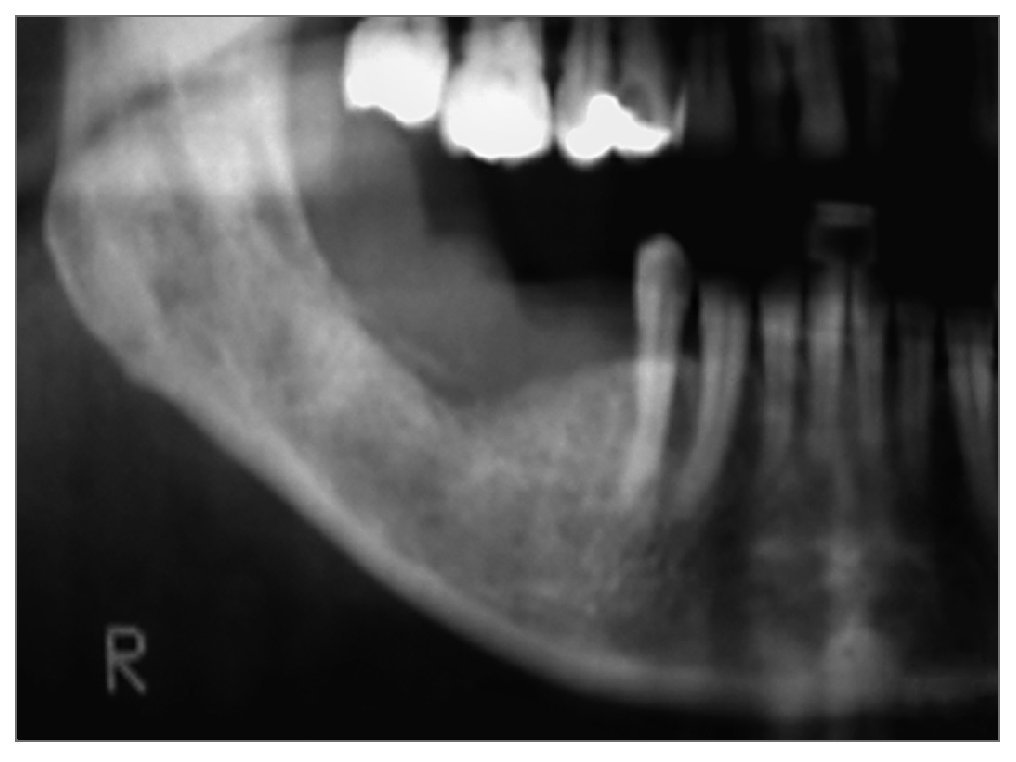

Una radiografía panorámica revelo un pequeño secuestro óseo y una ligera reabsorción de la cresta alveolar (fig. 1b).

Figura 1b. Radiografía panorámica que muestra un pequeño secuestro óseo y una ligera reabsorción del reborde alveolar.